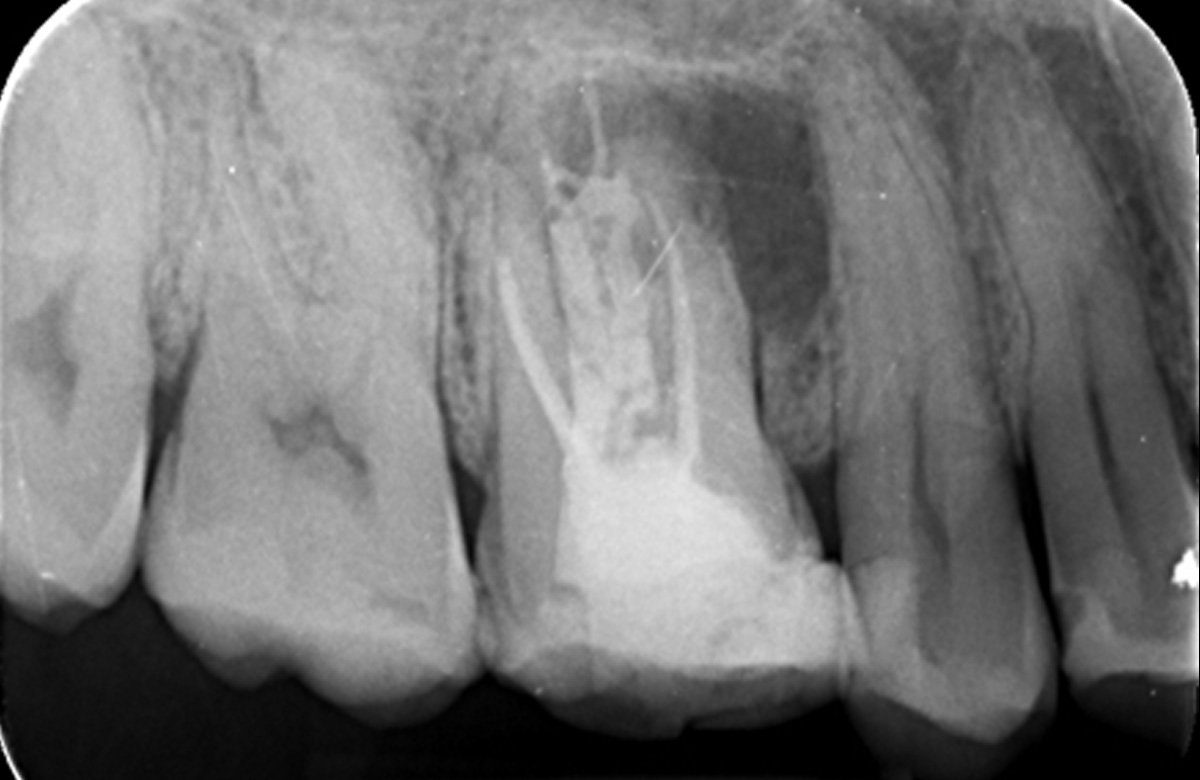

Pre operative periapical radiograph of the tooth 16

| Dental history | Patient has had previous root canal treatment over 5 years ago |

| Clinical evaluation | Tooth that is tender to percussion & palpation. Small fluctuant swelling associated with buccal alveolar mucosa |

| Diagnosis | Previously endodontically treated tooth with persisting chronic apical periodontitis |